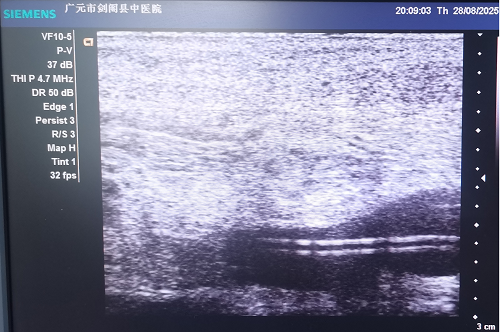

2025年8月28日剑阁县中医医院肿瘤科为一名右肺腺癌患者成功置入中长静脉导管,有效解决了该患者长期面临的输液困难问题,为后续治疗开辟了一条畅的“生命通道”。

患者,男,72岁,因“确诊右肺腺癌1+年,咳嗽、咳痰、气紧、纳差4天”于8月25日入院,神清,精神差,右侧肢体偏瘫,扶入病房。因病情需长期接受静脉输液治疗,但由于外周静脉条件极差,常规的浅静脉穿刺困难重重,不仅增加了患者的痛苦,也影响了治疗的顺利进行。面对这一棘手情况,主管医生及3名专科护士经过全面评估讨论,决定为患者实施中长静脉导管置入术。

在置入过程中,静脉治疗专科护士韩仕青凭借精湛的技术与丰富的经验,准确找到合适的穿刺位点,严格遵循无菌操作规范,成功将导管置入预定位置。经术后检查确认,导管位置理想,功能正常。目前,患者已通过该导管顺利接受输液治疗,未出现不良反应,治疗进程得以稳步推进。